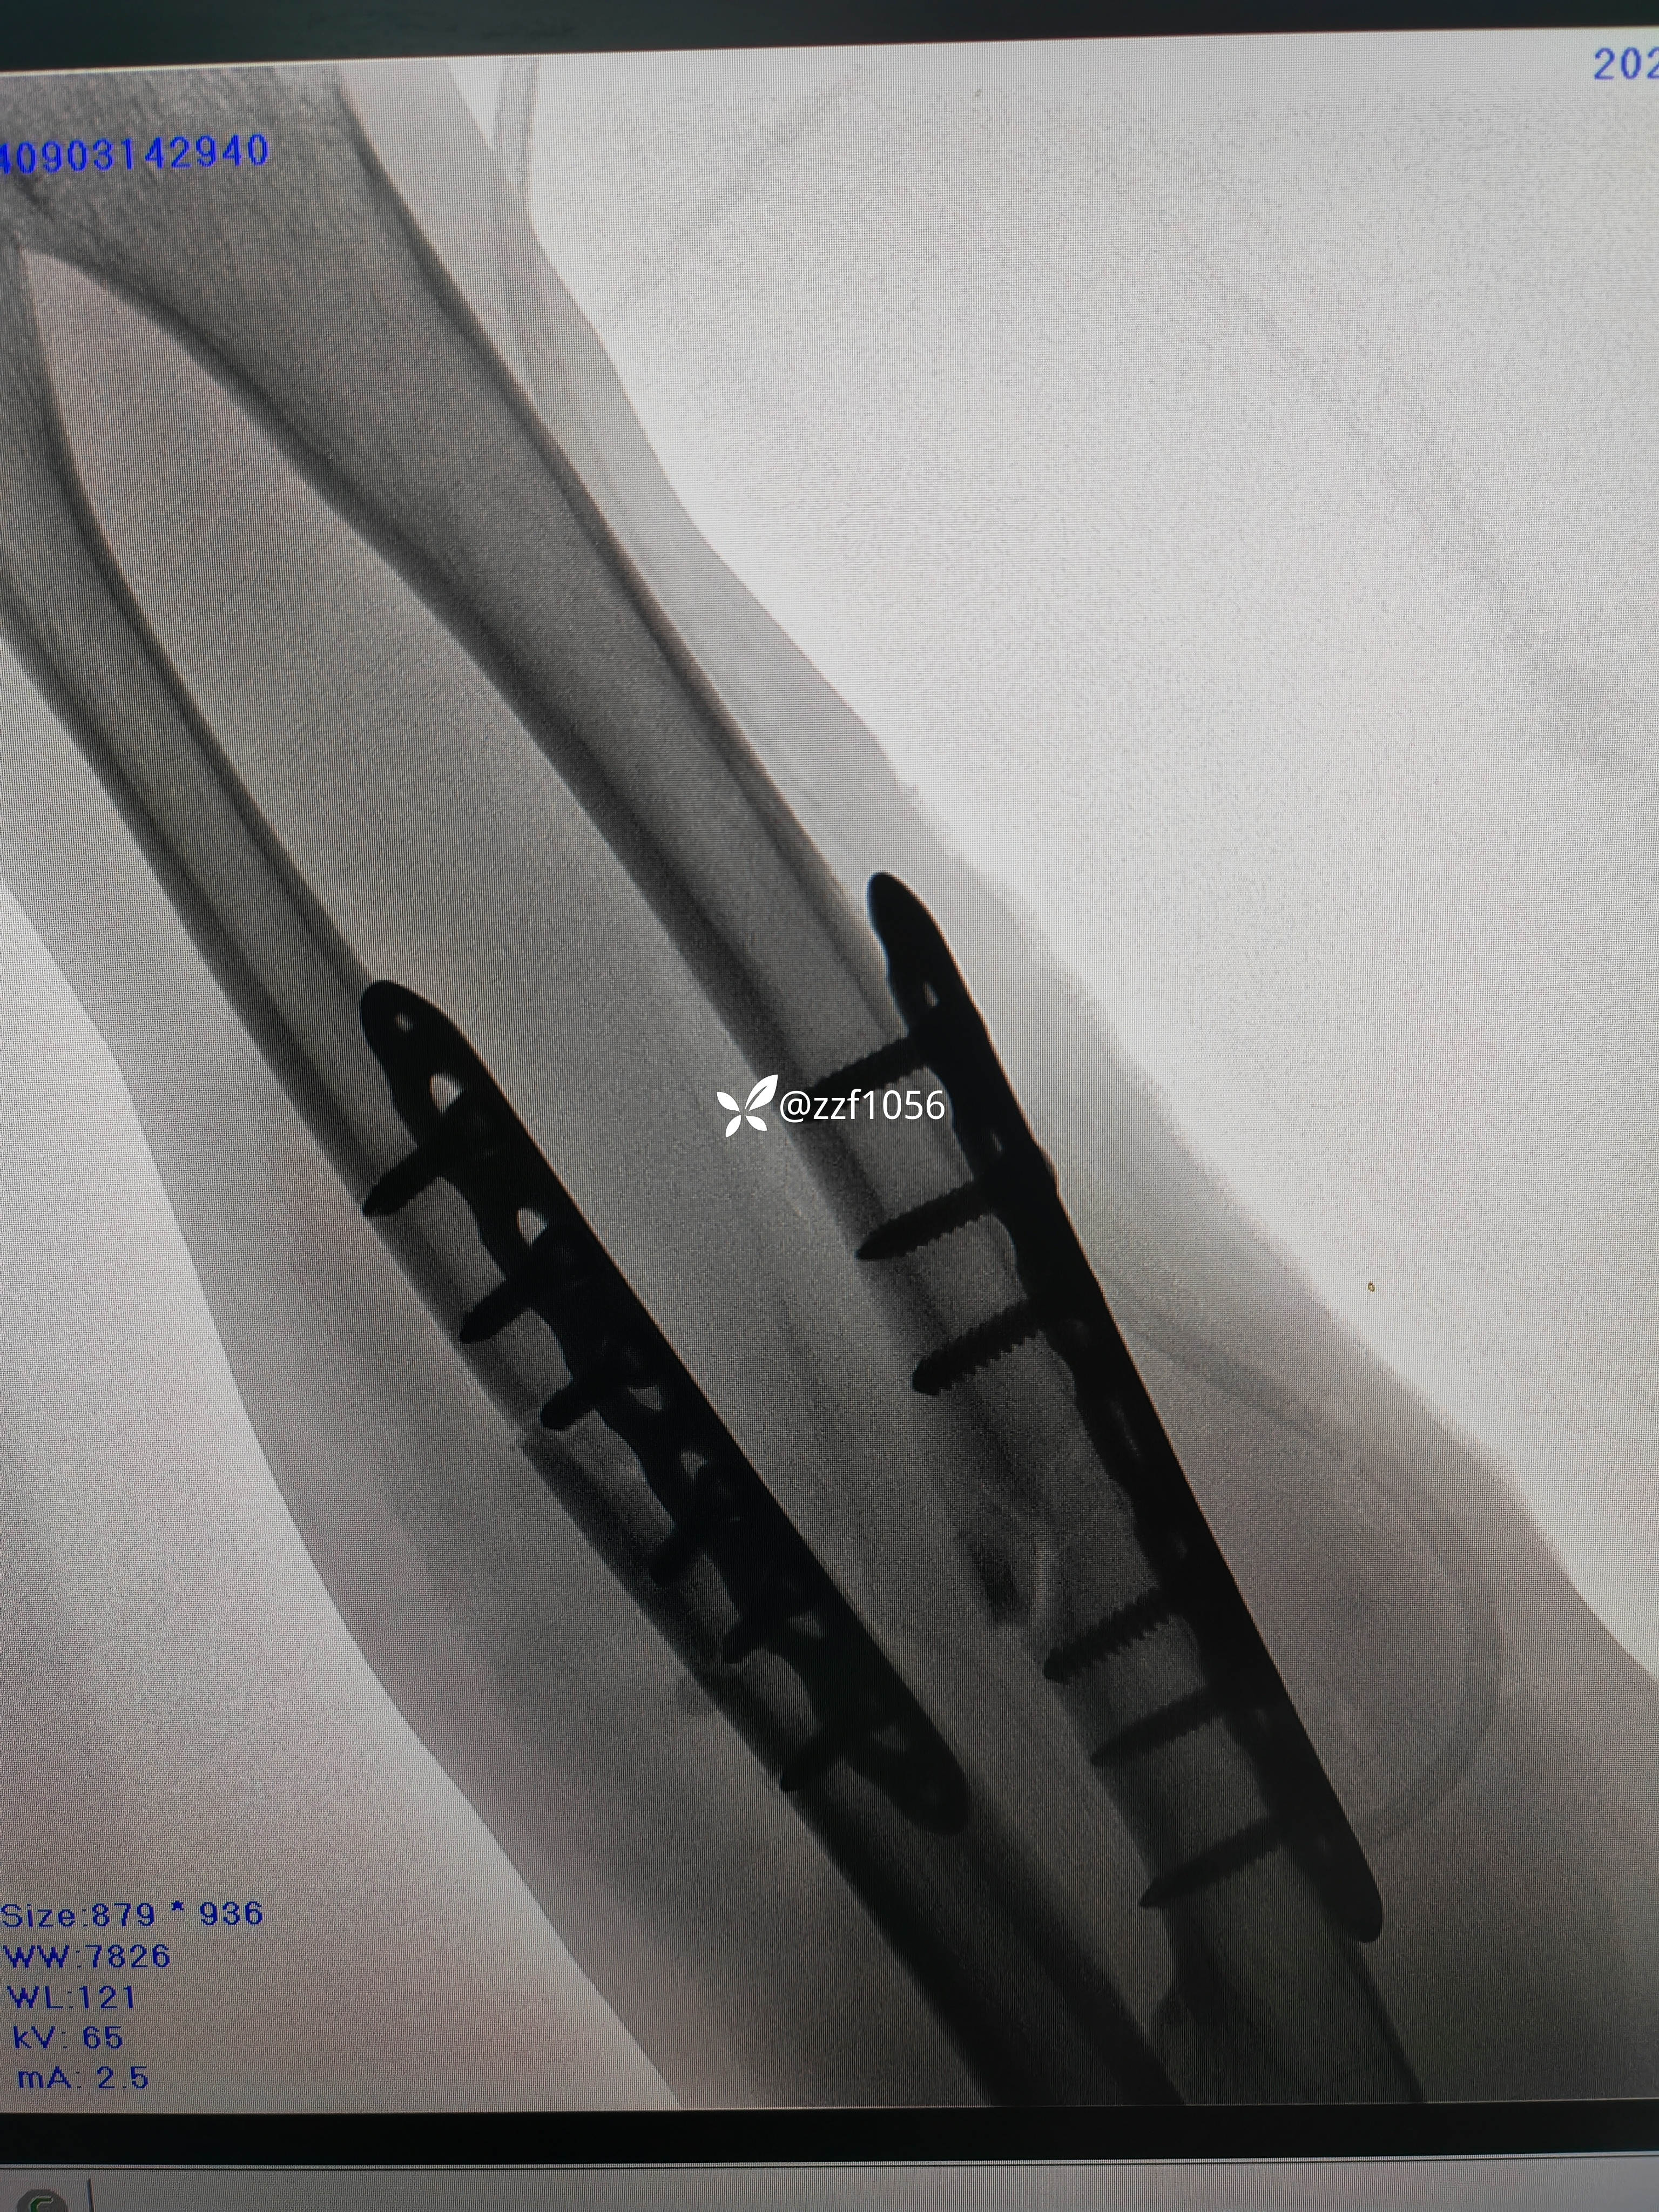

原计划桡骨行掌侧Henry,仔细测量后改背侧Thompson。